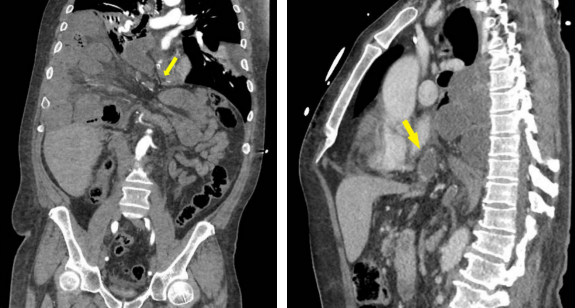

Two months after the operation, the patient was admitted to the emergency department due to diffuse abdominal and chest pain, vomiting, and hematemesis. The chest and abdominal CT scan showed herniation of several bowel loops into the right hemithorax [Figure 1]. Due to hemodynamic instability, an emergent laparotomy was performed finding severely distended small bowel with a hiatal hernia containing approximately 70 cm of small bowel herniated into the mediastinum. The esophageal hiatus was further opened in order to reduce the intestine to the abdomen. As the small bowel slowly recovered vitality, intestinal resection was not deemed necessary. The pillars of the diaphragm were then closed with interrupted stitches of non-absorbable suture, and the hiatal closure reinforced with a mesh. The patient recovered well from the operation and was discharged 10 days later.